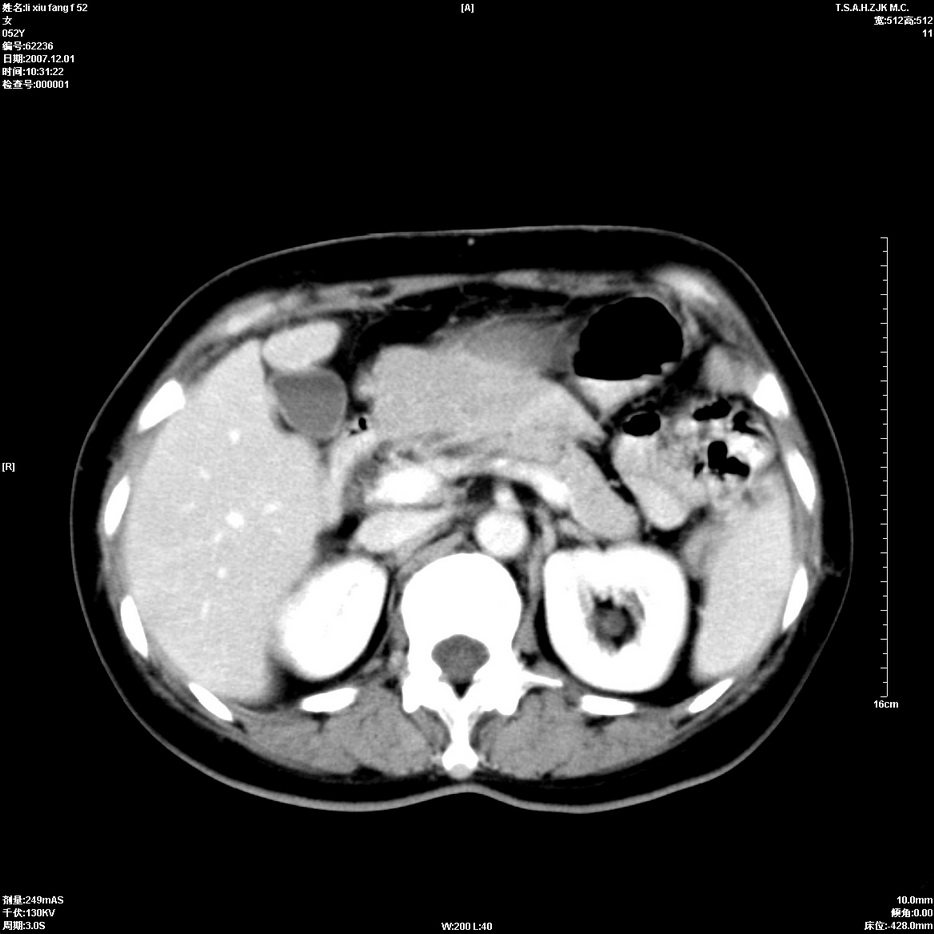

标题: CT12858:女,52岁,胎甲球蛋白861肝左叶占位,肝癌。下腔静 [打印本页]

标题: CT12858:女,52岁,胎甲球蛋白861肝左叶占位,肝癌。下腔静

肝左叶巨大低密度灶肿块,增强符合快进快出表现,有动静脉交通支;静脉期,下腔静脉内有充盈缺损,afp明显升高,支持肝癌并下腔静脉癌栓形成。

支持楼主   门静脉主干及左支癌栓形成

以下是引用拾荒者在2008-4-15 22:57:00的发言:[br]肝左叶巨大低密度灶肿块,增强符合快进快出表现,有动静脉交通支;静脉期,下腔静脉内有充盈缺损,afp明显升高,支持肝癌并下腔静脉癌栓形成。